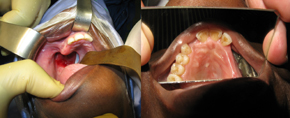

The patient's cleft palate

Then & now: The patient's cleft palate (left) and full closure (right) a month later. (Images provided by Dr George Vicatos.)   Turning the screws: After the operation (from left) Dr   Rushdi Hendricks, Dr George Vicatos and James   Boonzaier move the distractor's 'coach' along the   track.